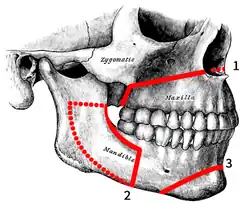

Osteotomies of the jaws:

1. Le Fort I 2. Bilateral Sagittal Split 3. Genioplasty 4. IMDO 5. GenioPaully 6. Custom PEEK 7. SARME 8. Custom BIMAX 9. Super BIMAX | |

Originally coined by Harold Hargis, it was more widely popularised first in Germany and then most famously by Hugo Obwegeser who developed the bilateral sagittal split osteotomy (BSSO). This surgery is also used to treat congenital conditions such as cleft palate.[2] Typically surgery is performed via the mouth, where jaw bone is cut, moved, modified, and realigned to correct malocclusion or dentofacial deformity. The word "osteotomy" means the division of bone by means of a surgical cut.

The "jaw osteotomy", either to the upper jaw or lower jaw (and usually both) allows (typically) an oral and maxillofacial surgeon to surgically align an arch of teeth, or the segment of a dental arch with its associated jawbone, relative to other segments of the dental arches. Working with orthodontists, the coordination of dental arches has primarily been directed to create a working occlusion. As such, orthognathic surgery is seen a secondary procedure supporting a more fundamental orthodontic objective.

Sagittal split osteotomy

This procedure is used to correct mandible retrusion and mandibular prognathism (over and under bite). First, a horizontal cut is made on the inner side of the ramus mandibulae, extending anterally to the anterior portion of the ascending ramus. The cut is then made inferiorly on the ascending ramus to the descending ramus, extending to the lateral border of the mandible in the area between the first and second molar. At this time, a vertical cut is made extending inferior to the body of the mandible, to the inferior border of the mandible. All cuts are made into the middle of the bone, where bone marrow is present. Then, a chisel is inserted into the pre existing cuts and tapped gently in all areas to split the mandible of the left and right side. From here, the mandible can be moved either forwards or backwards. If sliding backwards, the distal segment must be trimmed to provide room in order to slide the mandible backwards. Lastly, the jaw is stabilized using stabilizing screws that are inserted extra-orally. The jaw is then wired shut for approximately 4–5 weeks.[37]

Genioplasty osteotomy (intra-oral)

This procedure is used for the advancement (movement forward) or retraction (movement backwards) of the chin. First, incisions are made from the first bicuspid to the first bicuspid, exposing the mandible. Then, soft tissue of the mandible is detached from the bone; done by stripping attaching tissues. A horizontal incision is then made inferior to the first bicuspids, bilaterally, where bone cuts (osteotomies) are made vertically inferior, extending to the inferior border of the mandible, thereby detaching the bony segments of the mandible. The bony segments are stabilized with titanium plates; no fixation (binding of the jaw) necessary. If advancement is indicated for the chin, there are inert products available to implant onto the mandible, utilizing titanium screws, bypassing bone cuts.[38][39]

Rapid palatal expansion osteotomy

When a patient has a constricted (oval shape) maxilla, but normal mandible, many orthodontists request a rapid palatal expansion. This consists of the surgeon making horizontal cuts on the lateral board of the maxilla, extending anterally to the inferior border of the nasal cavity. At this time, a chisel designed for the nasal septum is utilized to detach the maxilla from the cranial base. Then, a pterygoid chisel, which is a curved chisel, is used on the left and right side of the maxilla to detach the pterygoid palates. Care must be taken as to not injure the inferior palatine artery. Prior to the procedure, the orthodontist has an orthopedic appliance attached to the maxilla teeth, bilaterally, extending over the palate with an attachment so the surgeon may use a hex-like screw to place into the device to push from anterior to posterior to start spreading the bony segments.[37] The expansion of the maxilla may take up to eight weeks with the surgeon advancing the expander hex lock, sideways (← →), once a week.